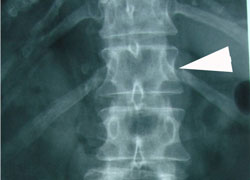

Thoracic spine subluxations can irritate the nerves of the disc, facet joints, and spinal nerves leaving the spine to cause pain in the mid-back that may even be felt around the sides and into the chest. At arrow, note the rotation subluxation which is an off-centering or rotation of the vertebra.